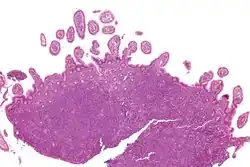

| Micrograph showing mantle cell lymphoma (bottom of image) in a biopsy of the terminal ileum. H&E stain. | |